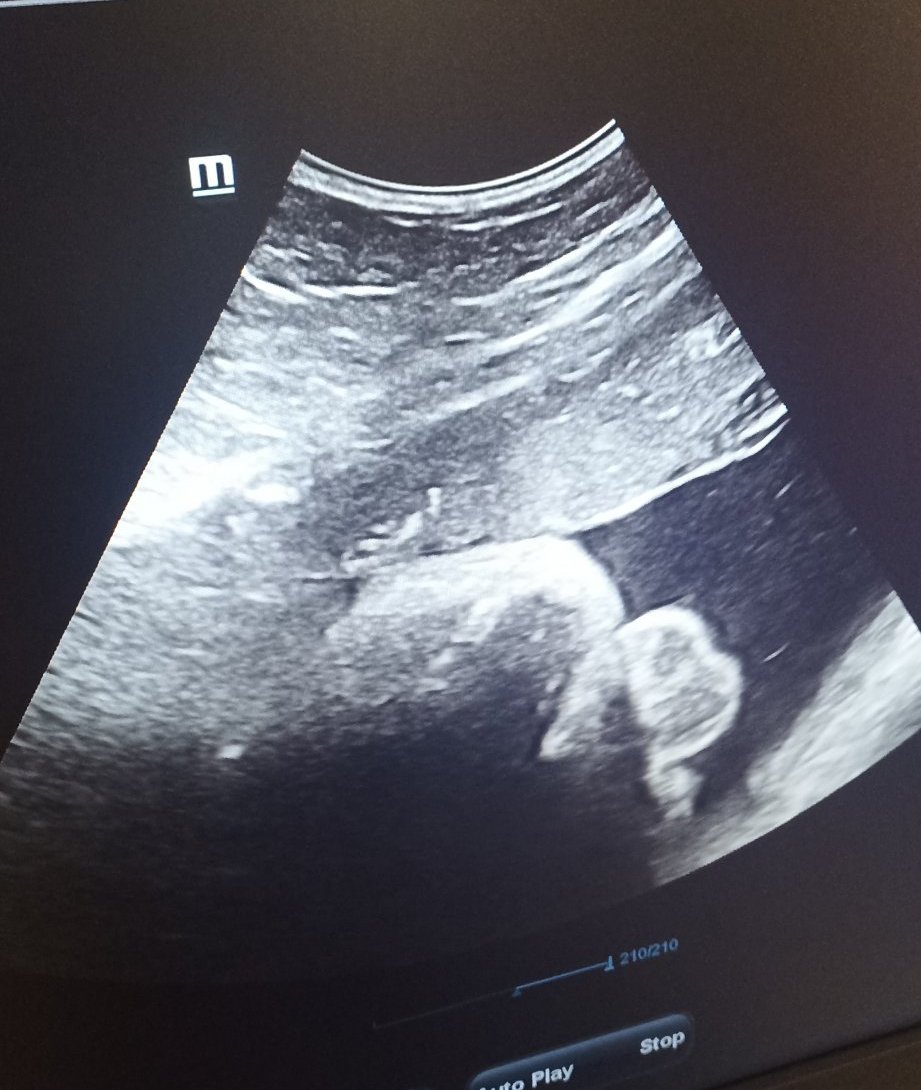

Днес минах през АГ-то. Готови сме,главата е долу,чакаме го да си тръгне сам. След 2 седмици пак съм на преглед,тогава вече ще съм 38-ма седмица. И ако сме имали съмнения за пол - вече нямаме . Снимката го показва много ясно! 🤣🤣🤣🤣🤣🤣🤣🤣🤣🤣🤣🤣🤣🤣

Shu34, хахаха. Весела снимка. Ясна е работата.